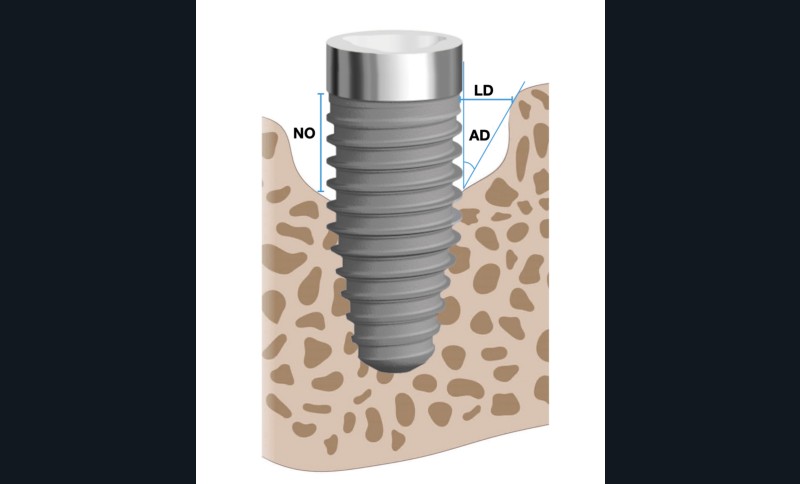

L’implant

- Péri-implantite sur l’implant 47, diagnostiquée en août 2022

- Poches de 6 à 7 mm

- Implant posé en 2017

- Nobel Replace Select RP (4,1 x 10 mm)